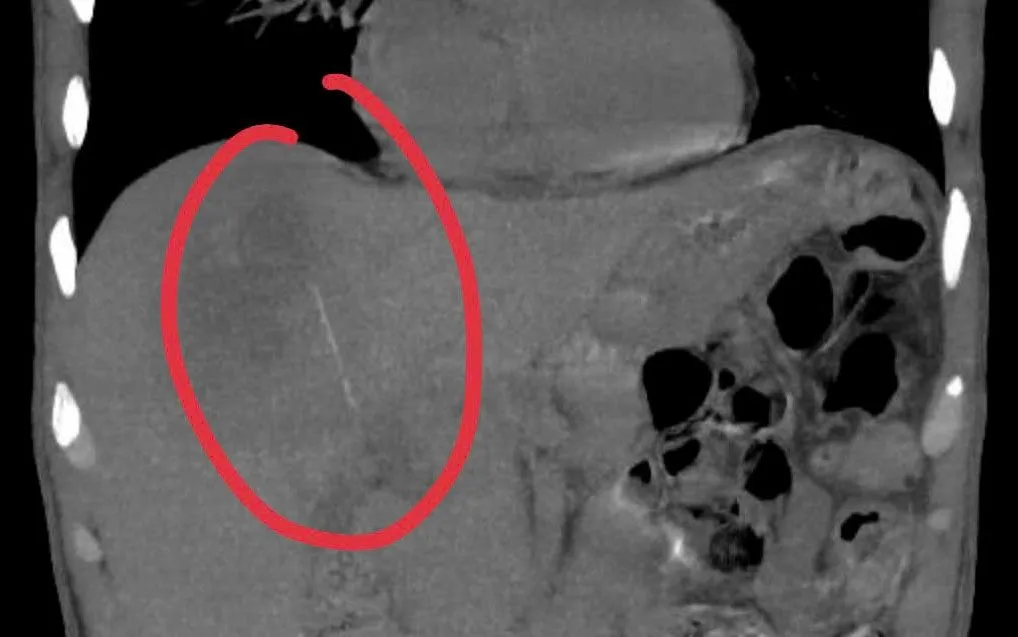

Qua siêu âm chi tiết và chụp CT scanner, bác sĩ phát hiện một dị vật dạng que dài khoảng 6-7cm nằm hoàn toàn trong nhu mô gan, kèm ổ áp xe sâu. Ngay sau đó, các chuyên khoa Nội tiêu hóa và Ngoại Gan Mật Tụy hội chẩn, quyết định phẫu thuật lấy dị vật và dẫn lưu ổ mủ.

ThS.BS Trần Đình Quốc, Khoa Ngoại Gan Mật Tụy, cho biết ca mổ phức tạp do ổ áp xe nằm sát cơ hoành và các mạch máu lớn. Ban đầu dự kiến mổ nội soi nhưng phải chuyển sang mổ mở để đảm bảo an toàn. Dị vật lấy ra là một cây tăm tre.